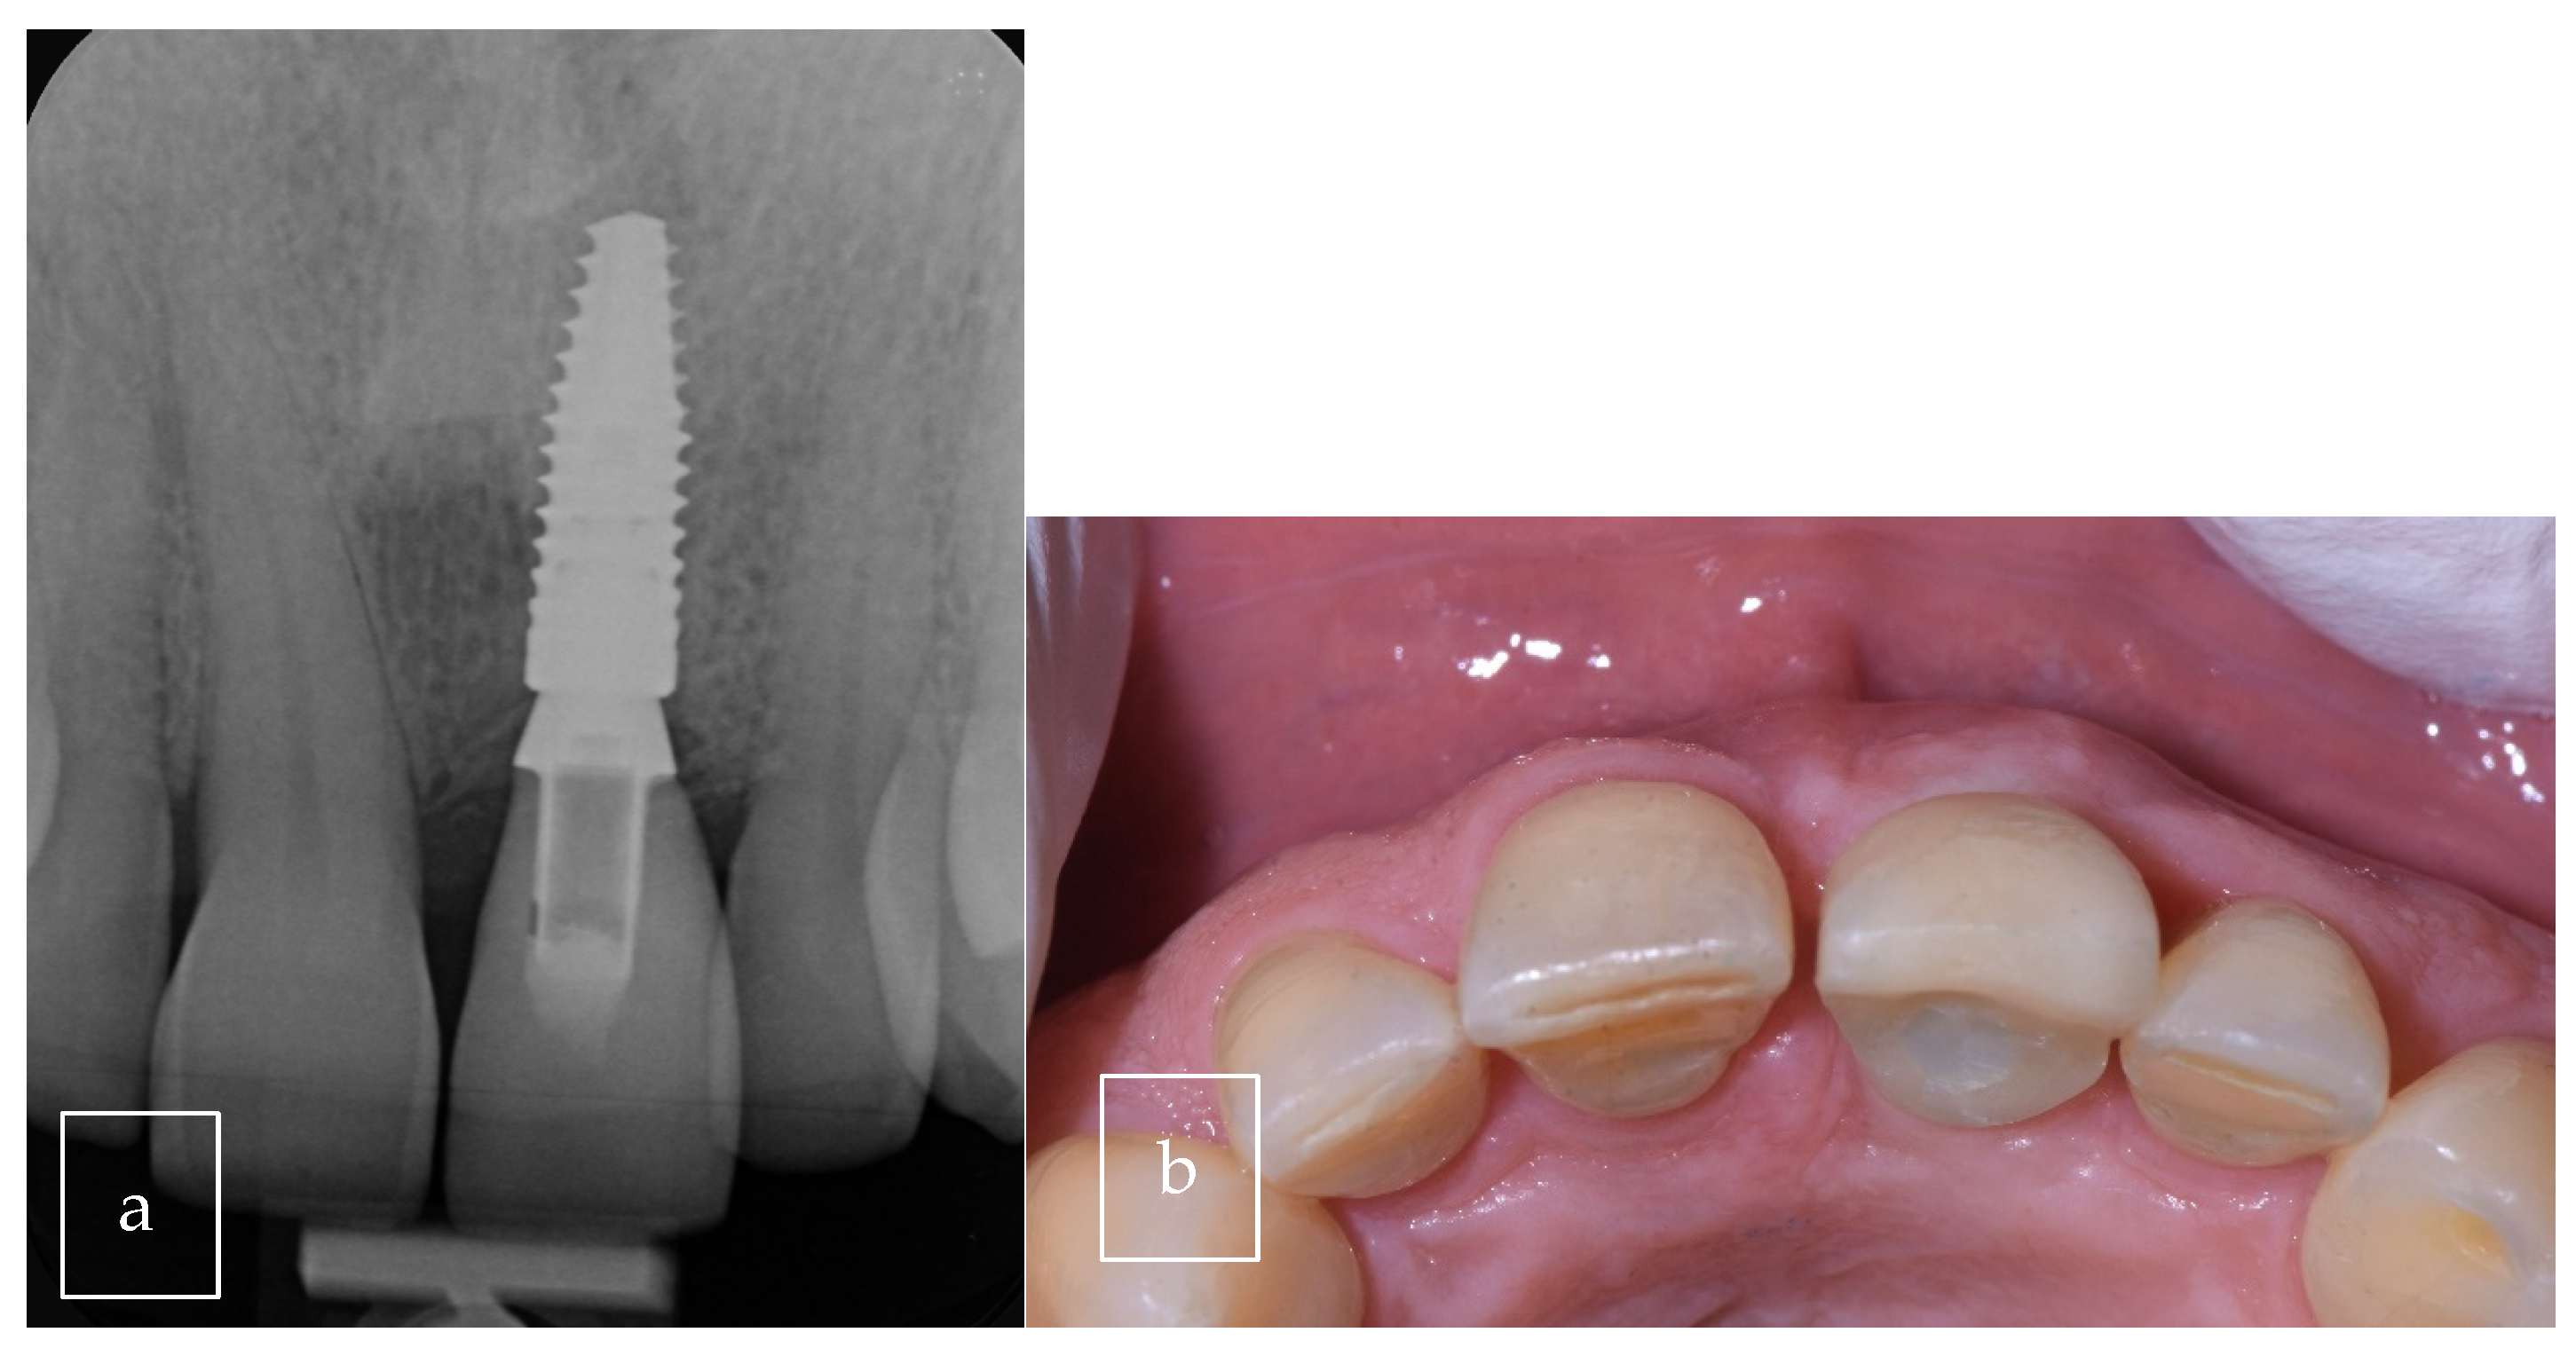

| Our case | Case report | 1 | M | 63 | Asymptomatic | Right palate | Surgical excision | 9 × 8 × 12.5 mm | Radiolucent |